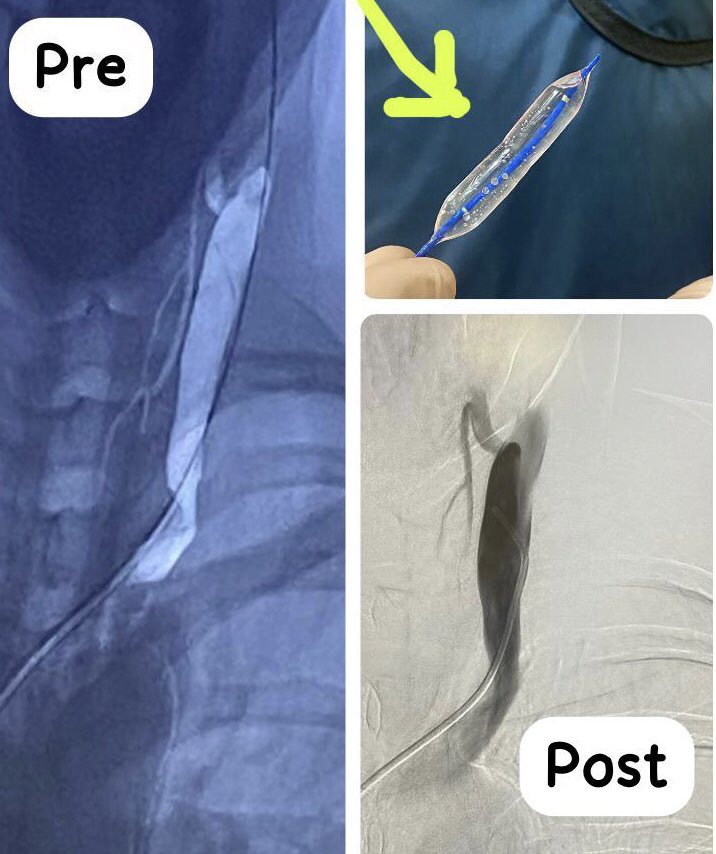

Why do you pretend not to see? Narrowing of the internal jugular vein causes a lot of #neurological symptoms. Chronic #cerebral venous insufficiency